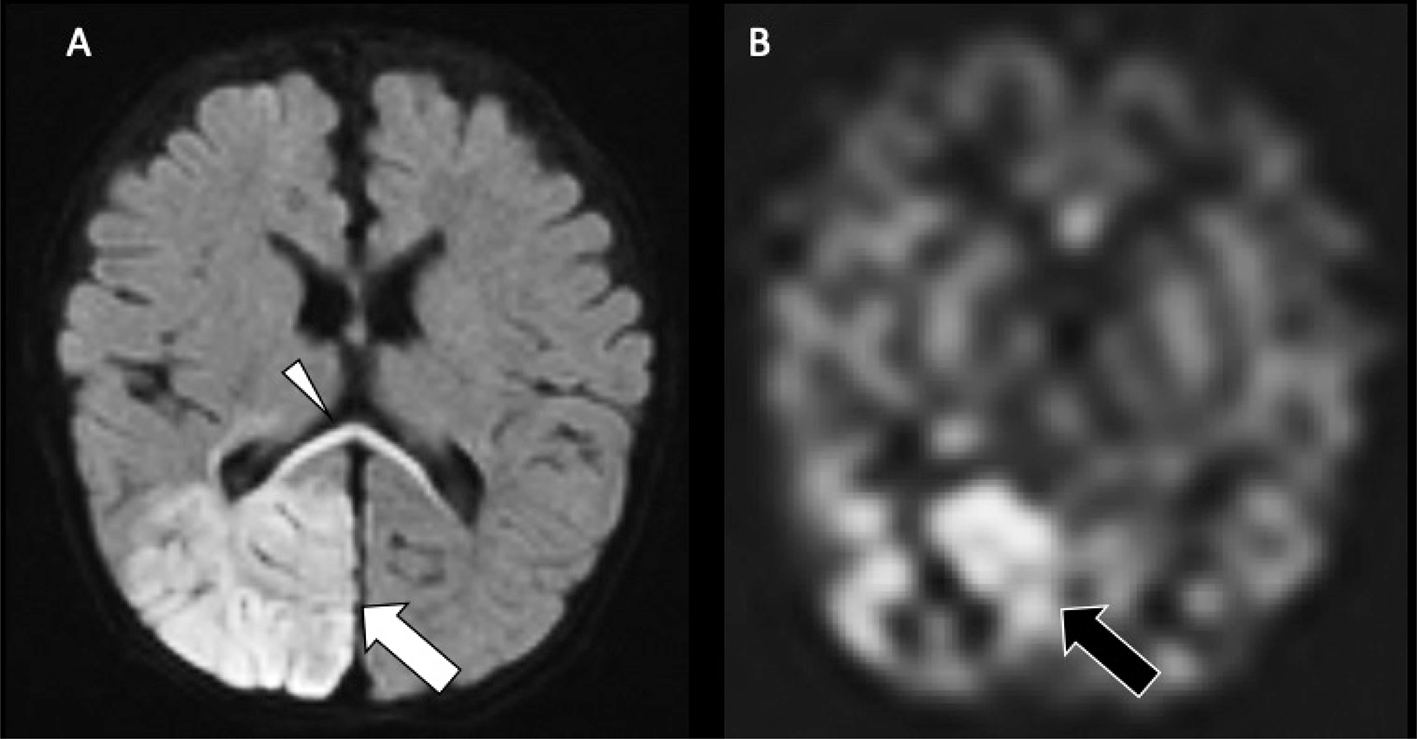

Perfusion imaging is not routinely used in neonatal stroke for technical reasons––dynamic susceptibility contrast-enhanced (DSC) imaging requires a large, generally power-injected contrast bolus and noncontrast arterial spin labeling (ASL) perfusion is technically challenging in neonates in part due to the faster heart rate––and because it does not presently alter patient management in most cases, although paradigms for use of neonatal perfusion are emerging (19). ASL can be used to assess perfusion without the need for intravenous contrast, with pseudocontinuous tagging schemes (pCASL) and ideally flexible prescription of post-label delays preferred (66). Compared to the core and penumbral hypoperfusion seen in older children and adults, neonates often demonstrate hyperperfusion within the region of decreased ADC (Figure 7), with little evidence of adjacent hypoperfusion, which may be related to reperfusion or seizure-associated neuronal hyperexcitability (67). Hypoperfusion may be more common in venous stroke (67).

Fig 7

Figure 7. Neonatal arterial ischemic infarction. DWI (A) demonstrates reduced diffusion in the right PCA territory (white arrow), from acute infarct, as well as the callosal splenium (white arrowhead), representing acute network injury, with increased perfusion on Arterial Spin Labeling (ASL) perfusion (black arrow) (B). Case courtesy of Dr. Tamara Feygin, Department of Radiology, Children’s Hospital of Philadelphia.